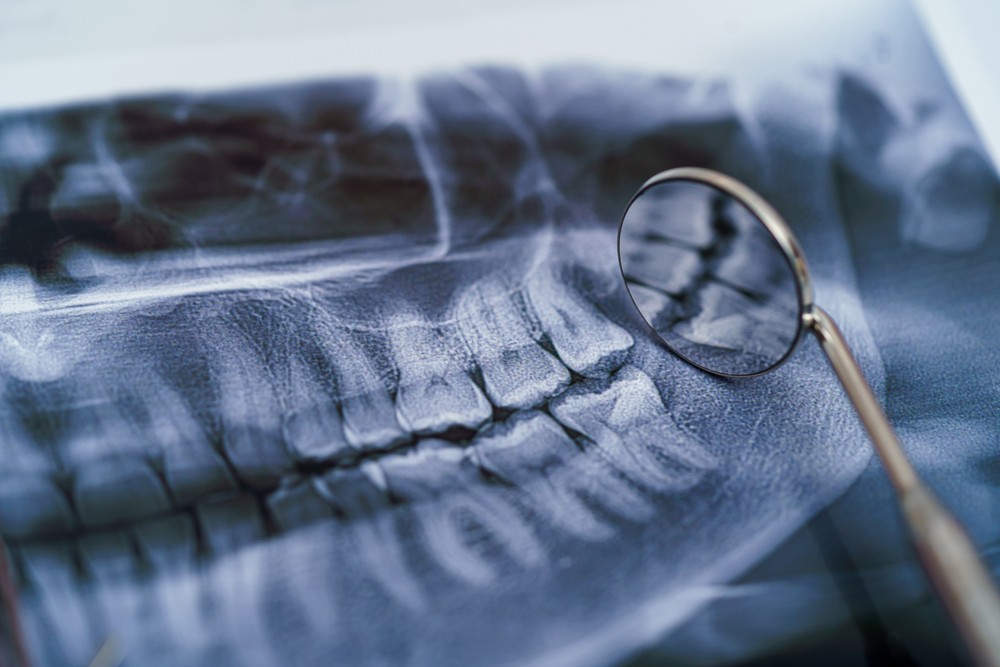

Multe boli ale dinților și ale țesuturilor înconjurătoare pot fi observate doar pe raze X, cum ar fi cariile interdentare, infecțiile radiculare (granuloame, chisturi), fracturile dentare și resorbția osului maxilarului din cauza leziunii parodontale.

Întregul proces, inclusiv imprimarea cu raze X, durează până la 10 minute și este important pentru a realiza un tratament endodontic precis.